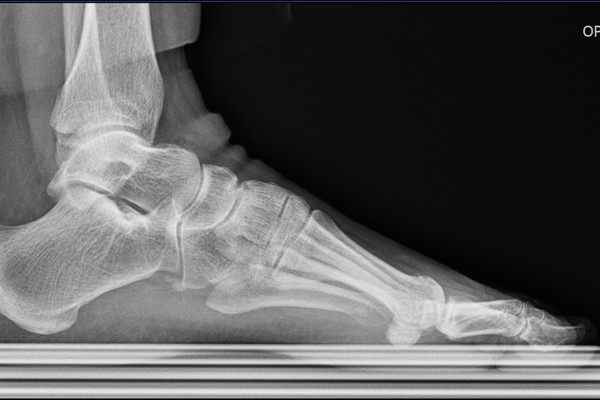

반면, 좌측 발에는 골극이 보이지 않습니다.